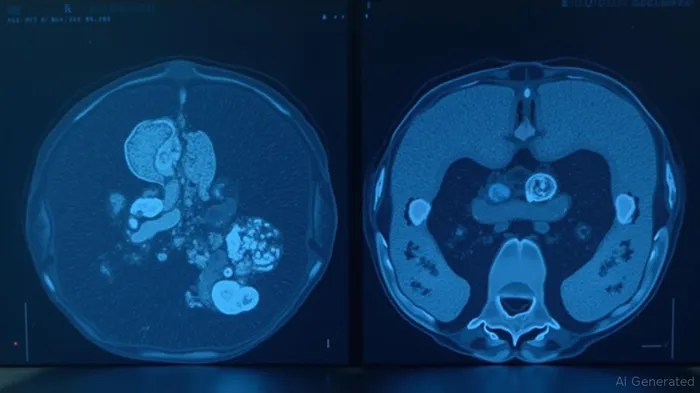

2. [68Ga]PSV377: A Diagnostic Breakthrough for FAP-α Tumors

Complementing its therapeutic pipeline is Perspective's [68Ga]PSV377, a PET imaging agent targeting fibroblast activation protein-α (FAP-α). FAP-α is overexpressed in the tumor microenvironment of many solid tumors, including colorectal and pancreatic cancers. Key findings:

- Superior Imaging: In a first-in-human study, [68Ga]PSV377 outperformed standard FDG-PET in detecting metastatic colorectal cancer, showing higher tumor uptake and clearer delineation.

- Theranostic Synergy: When paired with a 212Pb-based therapeutic agent, this diagnostic tool enables real-time dosimetry adjustments, maximizing efficacy and safety.

This dual modality approach could transform treatment paradigms, enabling clinicians to first identify responsive tumors via PSV377 and then administer targeted therapy with precision.